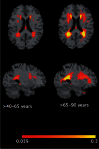

White matter hyperintensities are associated with increased risk of dementia and cognitive decline. The current study investigates the relationship between white matter hyperintensities burden and patterns of brain atrophy associated with brain ageing and Alzheimer's disease in a large populatison-based sample (n = 2367) encompassing a wide age range (20-90 years), from the Study of Health in Pomerania. We quantified white matter hyperintensities using automated segmentation and summarized atrophy patterns using machine learning methods resulting in two indices: the SPARE-BA index (capturing age-related brain atrophy), and the SPARE-AD index (previously developed to capture patterns of atrophy found in patients with Alzheimer's disease). A characteristic pattern of age-related accumulation of white matter hyperintensities in both periventricular and deep white matter areas was found. Individuals with high white matter hyperintensities burden showed significantly (P < 0.0001) lower SPARE-BA and higher SPARE-AD values compared to those with low white matter hyperintensities burden, indicating that the former had more patterns of atrophy in brain regions typically affected by ageing and Alzheimer's disease dementia. To investigate a possibly causal role of white matter hyperintensities, structural equation modelling was used to quantify the effect of Framingham cardiovascular disease risk score and white matter hyperintensities burden on SPARE-BA, revealing a statistically significant (P < 0.0001) causal relationship between them. Structural equation modelling showed that the age effect on SPARE-BA was mediated by white matter hyperintensities and cardiovascular risk score each explaining 10.4% and 21.6% of the variance, respectively. The direct age effect explained 70.2% of the SPARE-BA variance. Only white matter hyperintensities significantly mediated the age effect on SPARE-AD explaining 32.8% of the variance. The direct age effect explained 66.0% of the SPARE-AD variance. Multivariable regression showed significant relationship between white matter hyperintensities volume and hypertension (P = 0.001), diabetes mellitus (P = 0.023), smoking (P = 0.002) and education level (P = 0.003). The only significant association with cognitive tests was with the immediate recall of the California verbal and learning memory test. No significant association was present with the APOE genotype. These results support the hypothesis that white matter hyperintensities contribute to patterns of brain atrophy found in beyond-normal brain ageing in the general population. White matter hyperintensities also contribute to brain atrophy patterns in regions related to Alzheimer's disease dementia, in agreement with their known additive role to the likelihood of dementia. Preventive strategies reducing the odds to develop cardiovascular disease and white matter hyperintensities could decrease the incidence or delay the onset of dementia.